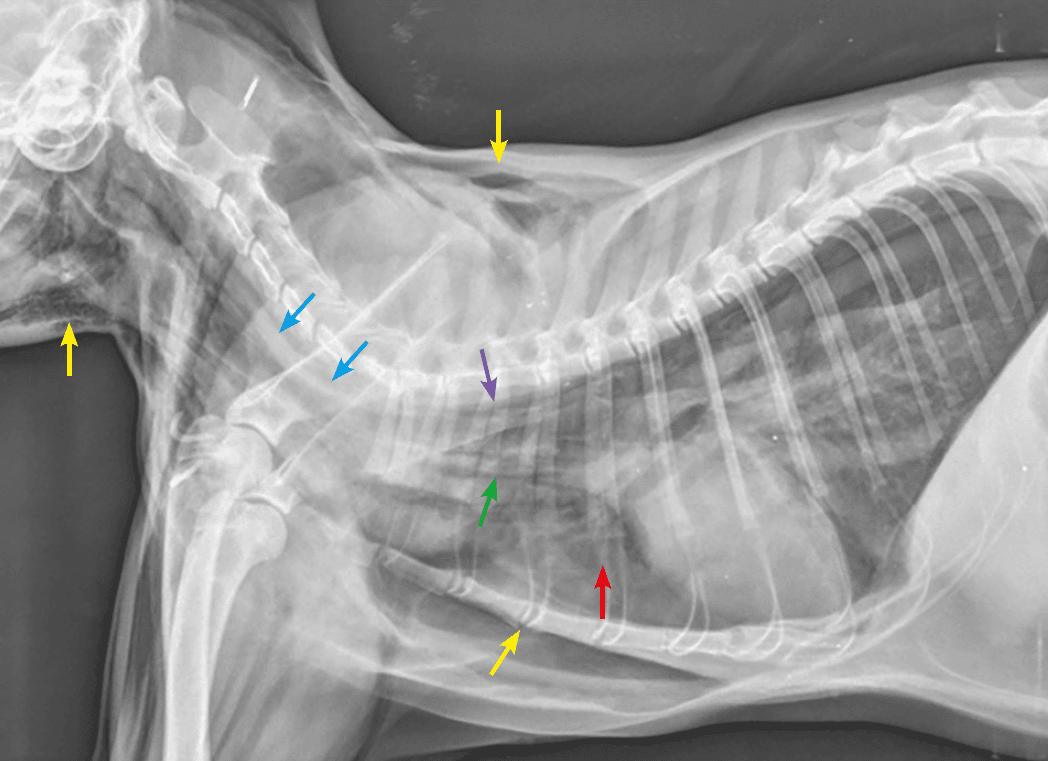

La rottura tracheale intratoracica nel gatto è rara ma grave. Una tracheoscopia consente di confermare la diagnosi e valutare la gravità delle lesioni. Il trattamento d’elezione è chirurgico e dev’essere intrapreso non appena lo stato clinico dell’animale lo consente.

Un caso di idronefrosi bilaterale in un gatto che ha comportato l’applicazione di subcutaneous ureteral bypass supporta la consapevolezza dell’importanza della diagnosi precoce di malattia renale al fine di valutare al meglio come poter intervenire per rallentarne la progressione.

I concetti chiave per lo studio radiografico dell’apparato gastrointestinale sono stati spiegati durante un seminario che si è focalizzato sulla lettura delle immagini radiografiche in corso di patologie da trattare con urgenza.